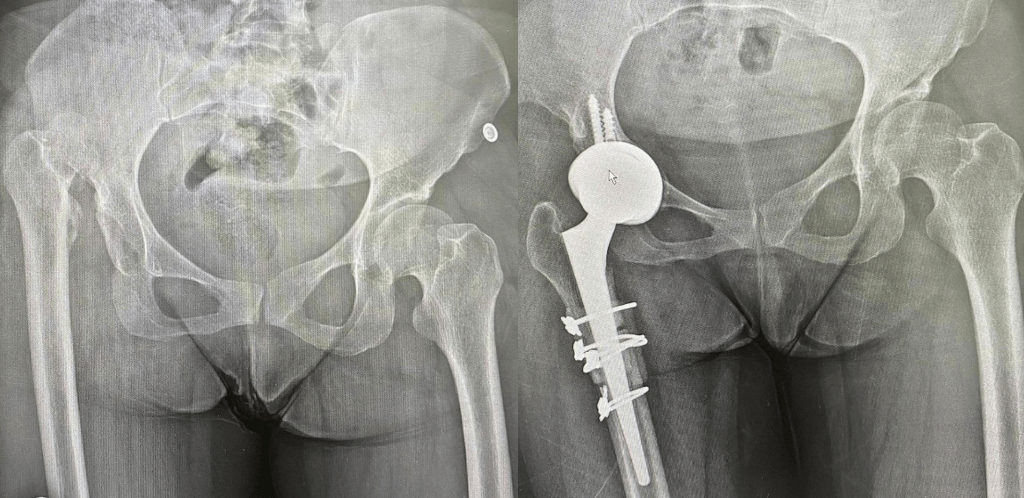

Замена таз сустава

Замена таз сустава 113 фотографий